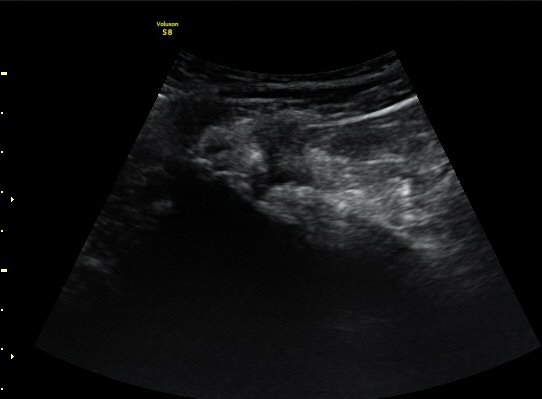

ÃÊÀ½ÆÄ °Ë»ç

¾ûµ¢ÀÌ °üÀý Á¾´Ü¸é°Ë»ç¿¡¼­ ƯÀÌ ¼Ò°ßÀ» º¸ÀÌÁö ¾ÊÀ½(»çÁø 1).

ŽÃËÀÚ¸¦ ¾ûµ¢ÀÌ °üÀý ¿ÜÃø Á¾´Ü¸é°Ë»ç ½Ã ÀüÇÏÀ屨(AIIS)¿¡¼­ ¼®È¸È­¼º À½¿µÀÌ °üÂûµÊ(»çÁø 2, 3).

¼±»óŽÃÊÀÚ¸¦ ÀÌ¿ëÇÑ °Ë»ç¿¡¼­ ÀüÇÏÀ屨ÀÇ ´ëÅðÁ÷±Ù ±â½ÃºÎ¿¡ ¼®È¸È­ À½¿µÀÌ ¶Ñ·ÈÈ÷

°üÂûµÊ(»çÁø 4, 5).